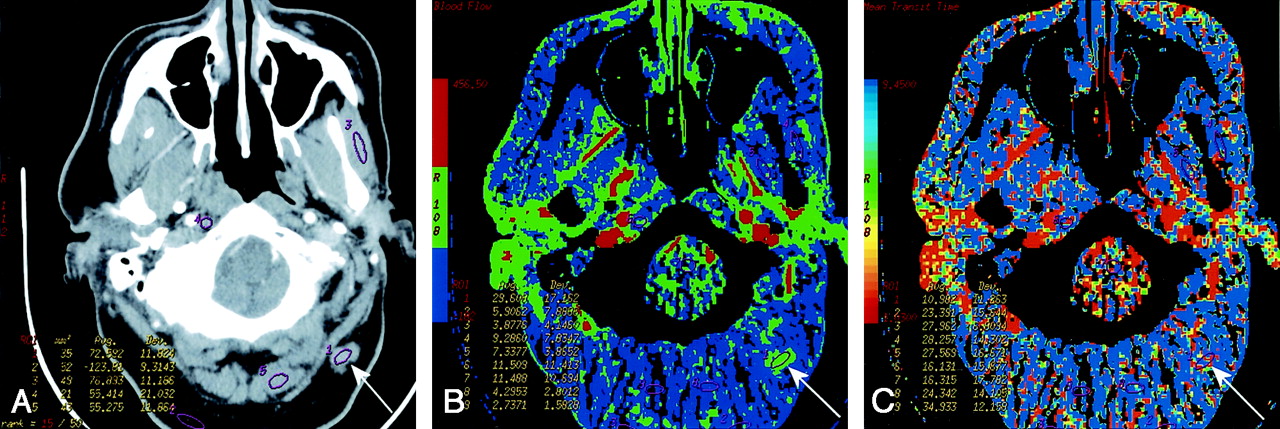

Patient 12 with primary gingival squamous cell cancer.

A, Contrast-enhanced neck CT scan shows a mass on both sides of the left mandibular body (arrows).

B, Lesion is more conspicuous on the CTP functional map, which reveals a high blood flow of 96–144 mL/100 g/min. Scale from red to blue corresponds to decreasing flow.

C, CTP functional map shows that the lesion has a short MTT of 2.1–5.4 seconds. Scale from red to blue corresponds to increasing MTT. The ROIs were placed within the lesion (8 and 9), paraspinal muscles (10), and left parotid gland (11).

Apart from numerical differences, malignant lesions tended to clearly stand out on the color maps (Fig 3), allowing for a quick overview of the whole plane. As with any other functional result, this finding should not be used in isolation, but rather, interpreted in conjunction with the anatomic images.